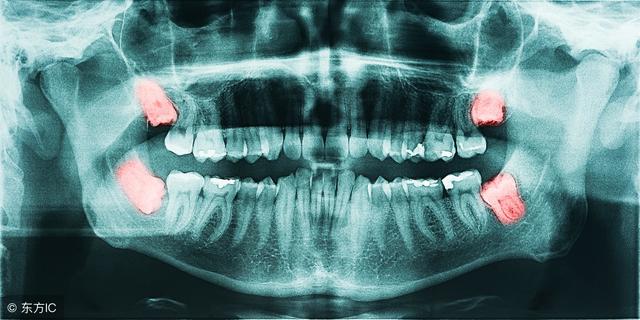

智齿就是口腔中的最后面的臼齿,有人会长,有人终生都不会长。不少人体验过智齿犯了,会疼的要命。

智齿的危害有哪些?

1. 影响正常咬合。阻生智齿的生长位置是不足的,也没有对应对颌牙齿,使之不能建立正常的咬合关系,长时间就会导致张口疼痛、磨牙等症状,对青壮年的身心影响较大。

4. 邻牙拥挤和松动。由于智齿的长歪没有足够的空间生长,就会挤压到相邻的牙齿,使相邻的牙齿松动,产生牙痛出血等症状。